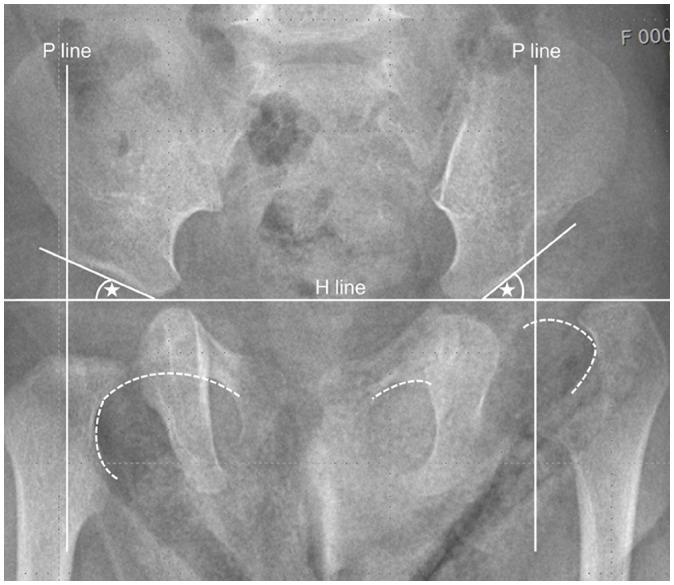

Developmental dysplasia of the hip is a condition characterized by hip joint instability due to acetabular dysplasia in infancy, necessitating precise ultrasound examination. Legg-Calvé-Perthes disease is caused by a temporary disruption in blood flow to the femoral head during childhood, progressing through avascular, fragmentation, re-ossification, and residual stages. Slipped capital femoral epiphysis is a condition where the femoral head shifts medially along the epiphyseal line during adolescence due to stress, such as weight-bearing. Differentiating between transient hip synovitis and septic arthritis may require joint fluid aspiration. Osteomyelitis can be associated with soft tissue edema and osteolysis. When multiple lesions are present, it is essential to distinguish between Langerhans cell histiocytosis and metastatic neuroblastoma. This review will introduce imaging techniques and typical findings for these conditions.

发育性髋关节发育不良是一种因婴儿期髋臼发育不良导致髋关节不稳定的病症,需要进行精确的超声检查。Legg-Calvé-Perthes病是由儿童期股骨头血液供应暂时中断引起的,历经缺血、碎裂、再骨化和残留阶段。股骨头骨骺滑脱是一种在青春期由于负重等压力导致股骨头沿骨骺线向内侧移位的病症。区分暂时性髋关节滑膜炎和化脓性关节炎可能需要进行关节液抽吸。骨髓炎可伴有软组织水肿和骨质溶解。当出现多个病灶时,区分朗格汉斯细胞组织细胞增多症和转移性神经母细胞瘤至关重要。本综述将介绍这些病症的影像学技术和典型表现。